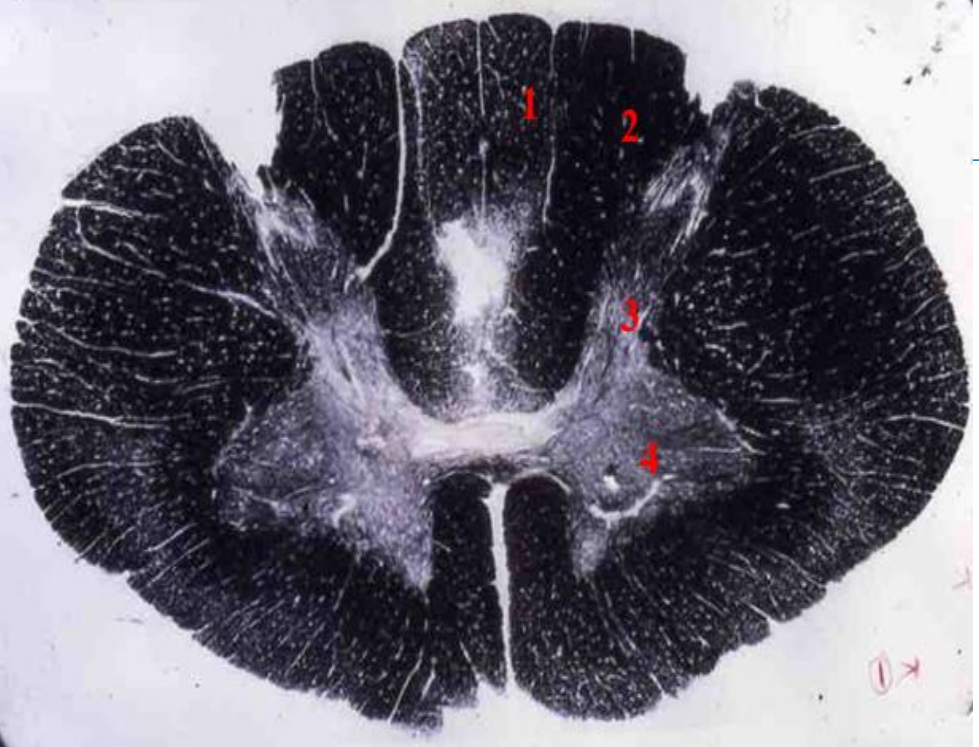

1

lumbar cord

- fibre tracts are few

- large anterior and posterior horns due to lumbar plexus

fasciculus gracilis

3

2

4

Q

A

anterior horn